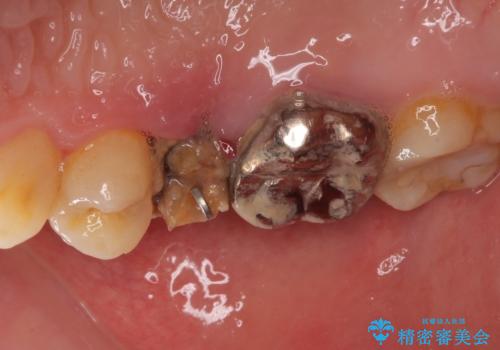

- 他院で大きな虫歯の歯を引っ張り出す治療中、あまりにも異臭がするとのことで来院された患者様です。

診査したところ、虫歯が広範囲で、粗造になった歯の表面に汚れがこびりついていました。また、歯根の半分以上の深さにまで亀裂が生じており、保存は不可能と診断しました。

抜歯後に治癒を待って、フルジルコニアブリッジにて補綴することとしました。